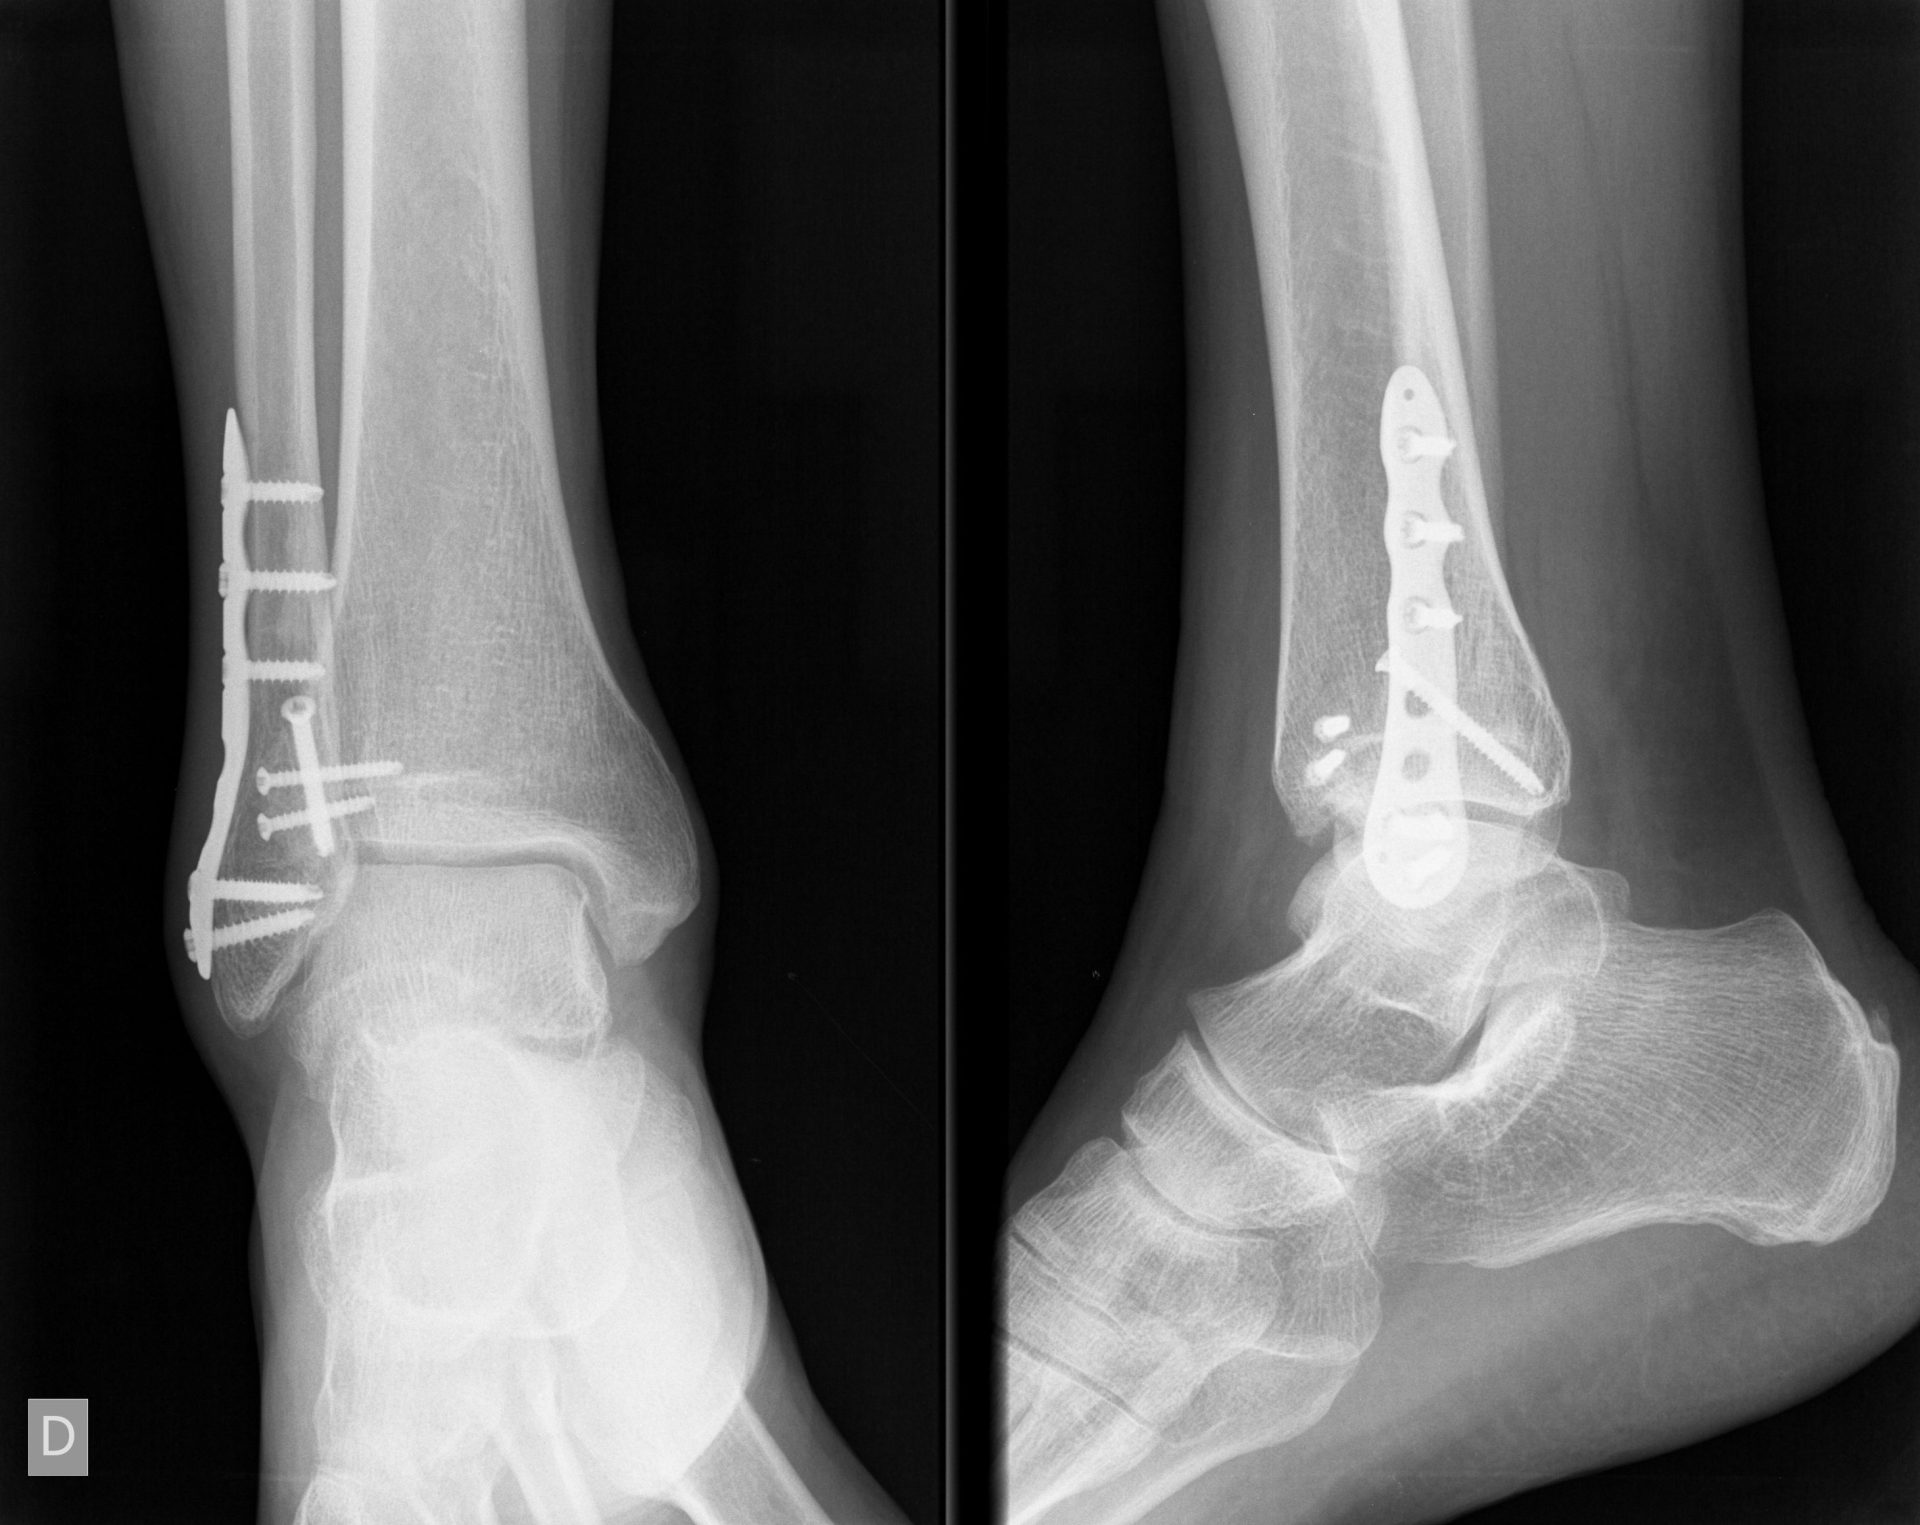

Una fractura de tobillo suele ser el resultado de una lesión por torsión, pero también puede ser causada por un golpe directo en el tobillo.

La gravedad de una fractura de tobillo varía. Las fracturas pueden abarcar desde pequeñas fisuras en los huesos hasta fracturas con varios fragmentos o con herida abierta exponiendo el hueso al exterior.

Son fracturas articulares, afectando a la tibia y/o al peroné y el tratamiento depende de los huesos afectados, localización del nivel de fractura y afectación de ligamentos.

Son lesiones graves, pues condicionan la movilidad del tobillo, por lo que su tratamiento debe ser cuidadoso en la reconstruccion de la articulación.

El tratamiento intentará restablecer la anatomía, siendo para ello necesaria la intervención quirúrgica y la reconstrucción con placas específicas y tornillos.